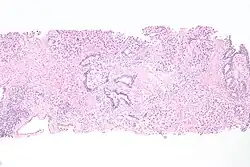

| Histopathology of transitional carcinoma of the urinary bladder. Transurethral biopsy. Hematoxylin and eosin stain. | |

_at_trigone.jpg) Histopathology of urothelial carcinoma of the urinary bladder, showing a nested pattern of invasion. Transurethral biopsy. H&E stain

Histopathology of urothelial carcinoma of the urinary bladder, showing a nested pattern of invasion. Transurethral biopsy. H&E stain -

_at_trigone.jpg) Histopathology of urothelial carcinoma of the urinary bladder.

Histopathology of urothelial carcinoma of the urinary bladder. -